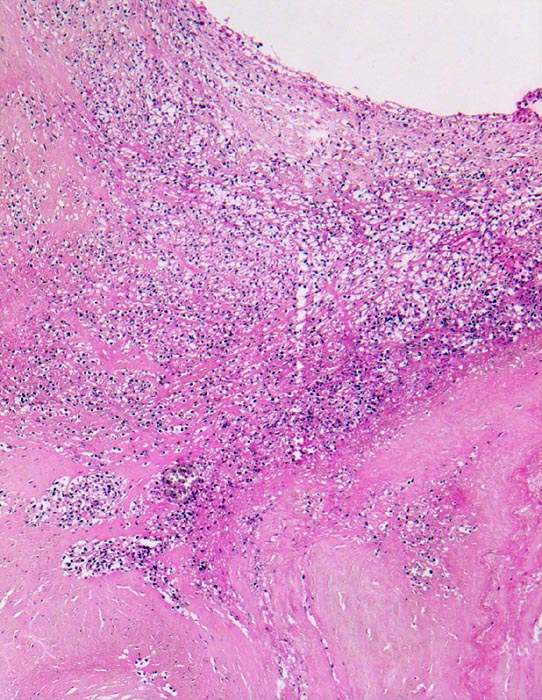

Histologisch findet sich bei ulzeropolypöser Endokarditis ein Fibrin-Thrombozytenthrombus, welcher von Bakterien durchsetzt ist (=Vegetation). Die Vegetation sitzt auf einem Klappendefekt an dessen Basis Granulationsgewebe einzusprossen beginnt, welches den Thrombus organisiert. Klappendefekte, Gefässeinsprossungen, verdickte Sehnenfäden (> 2848) oder Kommissurenverwachsungen (> 8389) der Taschenklappen weisen morphologisch auf eine abgeheilte Endokarditis hin.

• Längsschnitt durch Aorta, Aortenklappe und linkes Ventrikelmyokard.

• Ulzerierte Aortenklappe(ulcerosa).

• Dem ulzerierten Klappengerüst aufgelagerte polypöse Vegetation aus Fibrin und Granulozyten durchsetzt von blauen Kokkenbakterienkolonien (polyposa).

• Ausgedehnte frische Koagulationsnekrose (unsichtbare Zellkerne, Infiltrate neutrophiler Granulozyten) des linken Ventrikelmyokards unterhalb der Klappe.